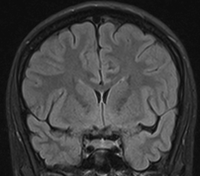

Den superiore flade af temporallappen grænser op mod Insula inferiore halvdel. Den forreste del af denne flade er konkav (planum polare) og matcher den anteriore inferiore konvekse form af Insula, mens den posteriore supriore flade en med plan (planum temporale). Denne forskel kan tydligt erkendes på coronale MR-skanningssnit (Fig. 5+6). Overgangen mellem den konkave og den plane den af temporallappens superiore flade markere lokalisationen af Heschel's gyrus. Heschel's gyrus har et skråt forløb fra antero-lateralt til postero-medialt. Lateralt findes Heschel's gyrus lige overfor gyrus postcentral i parietallappen adskilt af lateralfissuren. Følges Heschel's gyrus medialt posteriort peger den mod atrium af ventrikelsystem lige posteriort for thalamus (Fig. 4).